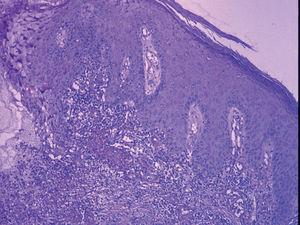

Un varón de 23 años, con antecedentes de dermatitis atópica y pie cavo bilateral corregido quirúrgicamente presentó un antecedente de un Mantoux positivo en 1995. En ese momento se instauró quimioprofilaxis con isoniazida, pero se tuvo que suspender al cabo de pocas semanas debido a una elevación grave de las transaminasas. El paciente presentó en 1999, un exantema varioliforme en la cara anterior de ambos miembros que se diagnosticó de foliculitis y fue tratado con doxiciclina con mejoría moderada. Al cabo de 9 meses presentó un episodio similar, pero en esta ocasión la evolución fue desfavorable, por lo que se remitió a nuestro servicio. En la primera consulta dermatológica se apreciaba una erupción diseminada, más o menos simétrica en miembros, con lesiones polievolutivas, pápulas, pústulas, escaras y cicatrices (fig. 1). La biopsia cutánea mostró una vasculitis granulomatosa necrosante (fig. 2), con focos granulomatosos con células gigantes (fig. 3). El cultivo micológico y bacteriológico de exudado y de material de biopsia fue negativo. La tinción de Ziehl fue negativa. La radiografía de tórax no mostró hallazgos patológicos. La bioquímica mostró una elevación moderada de las transaminasas. Finalmente, la PCR para micobacterias sobre material de biopsia resultó negativa. La prueba de Mantoux resultó necrótica. Se inició tratamiento con isoniazida 300 mg/día. A los 3 meses se suspendió el tratamiento por una elevación de transaminasas de cuatro veces sobre los valores básicos. En ese momento, la mejoría del cuadro había sido completa, y sólo se habían observado cicatrices varioliformes residuales en las piernas y las nalgas. En la última revisión de 2005 persistían las marcadas cicatrices residuales sin signos de actividad lesional reciente.

Fig. 3.--Foco granulomatoso en la periferia lesional. (Hematoxilina-eosina x400.)